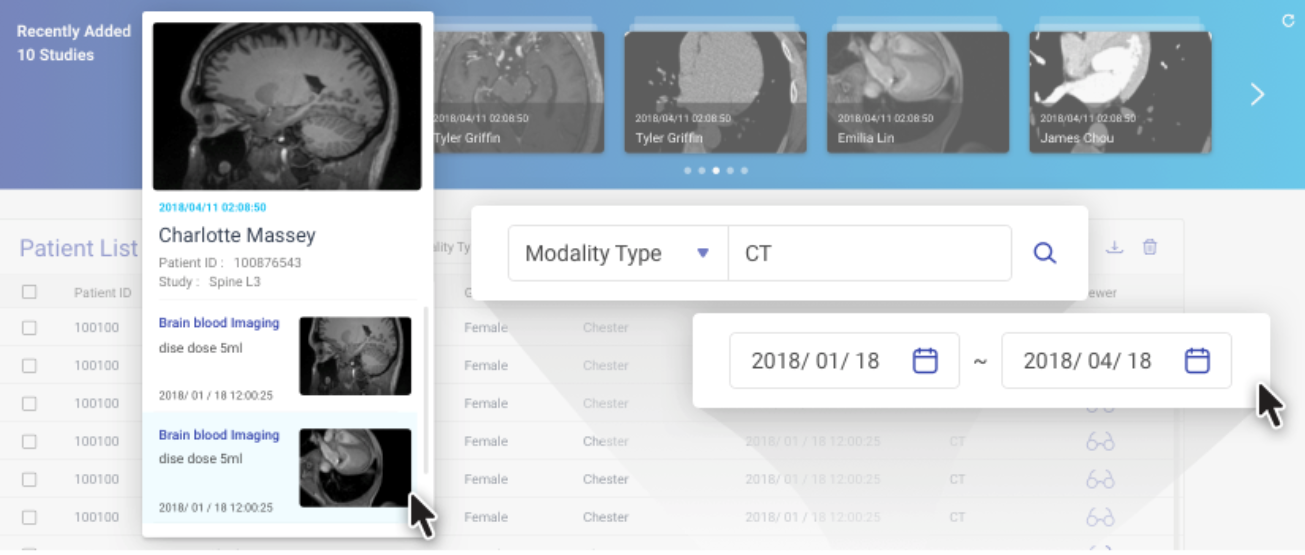

图像轮播

图像轮播显示为选定 PACS 服务器最新添加的 10 项患者研究。

选择 PACS 服务器,然后将鼠标指针悬停在图像上可查看研究和相应的图像系列。单击一个系列会在新的浏览器窗口中打开 DICOM Viewer。

指定设备类型和时间段可在图像轮播上显示相关研究。